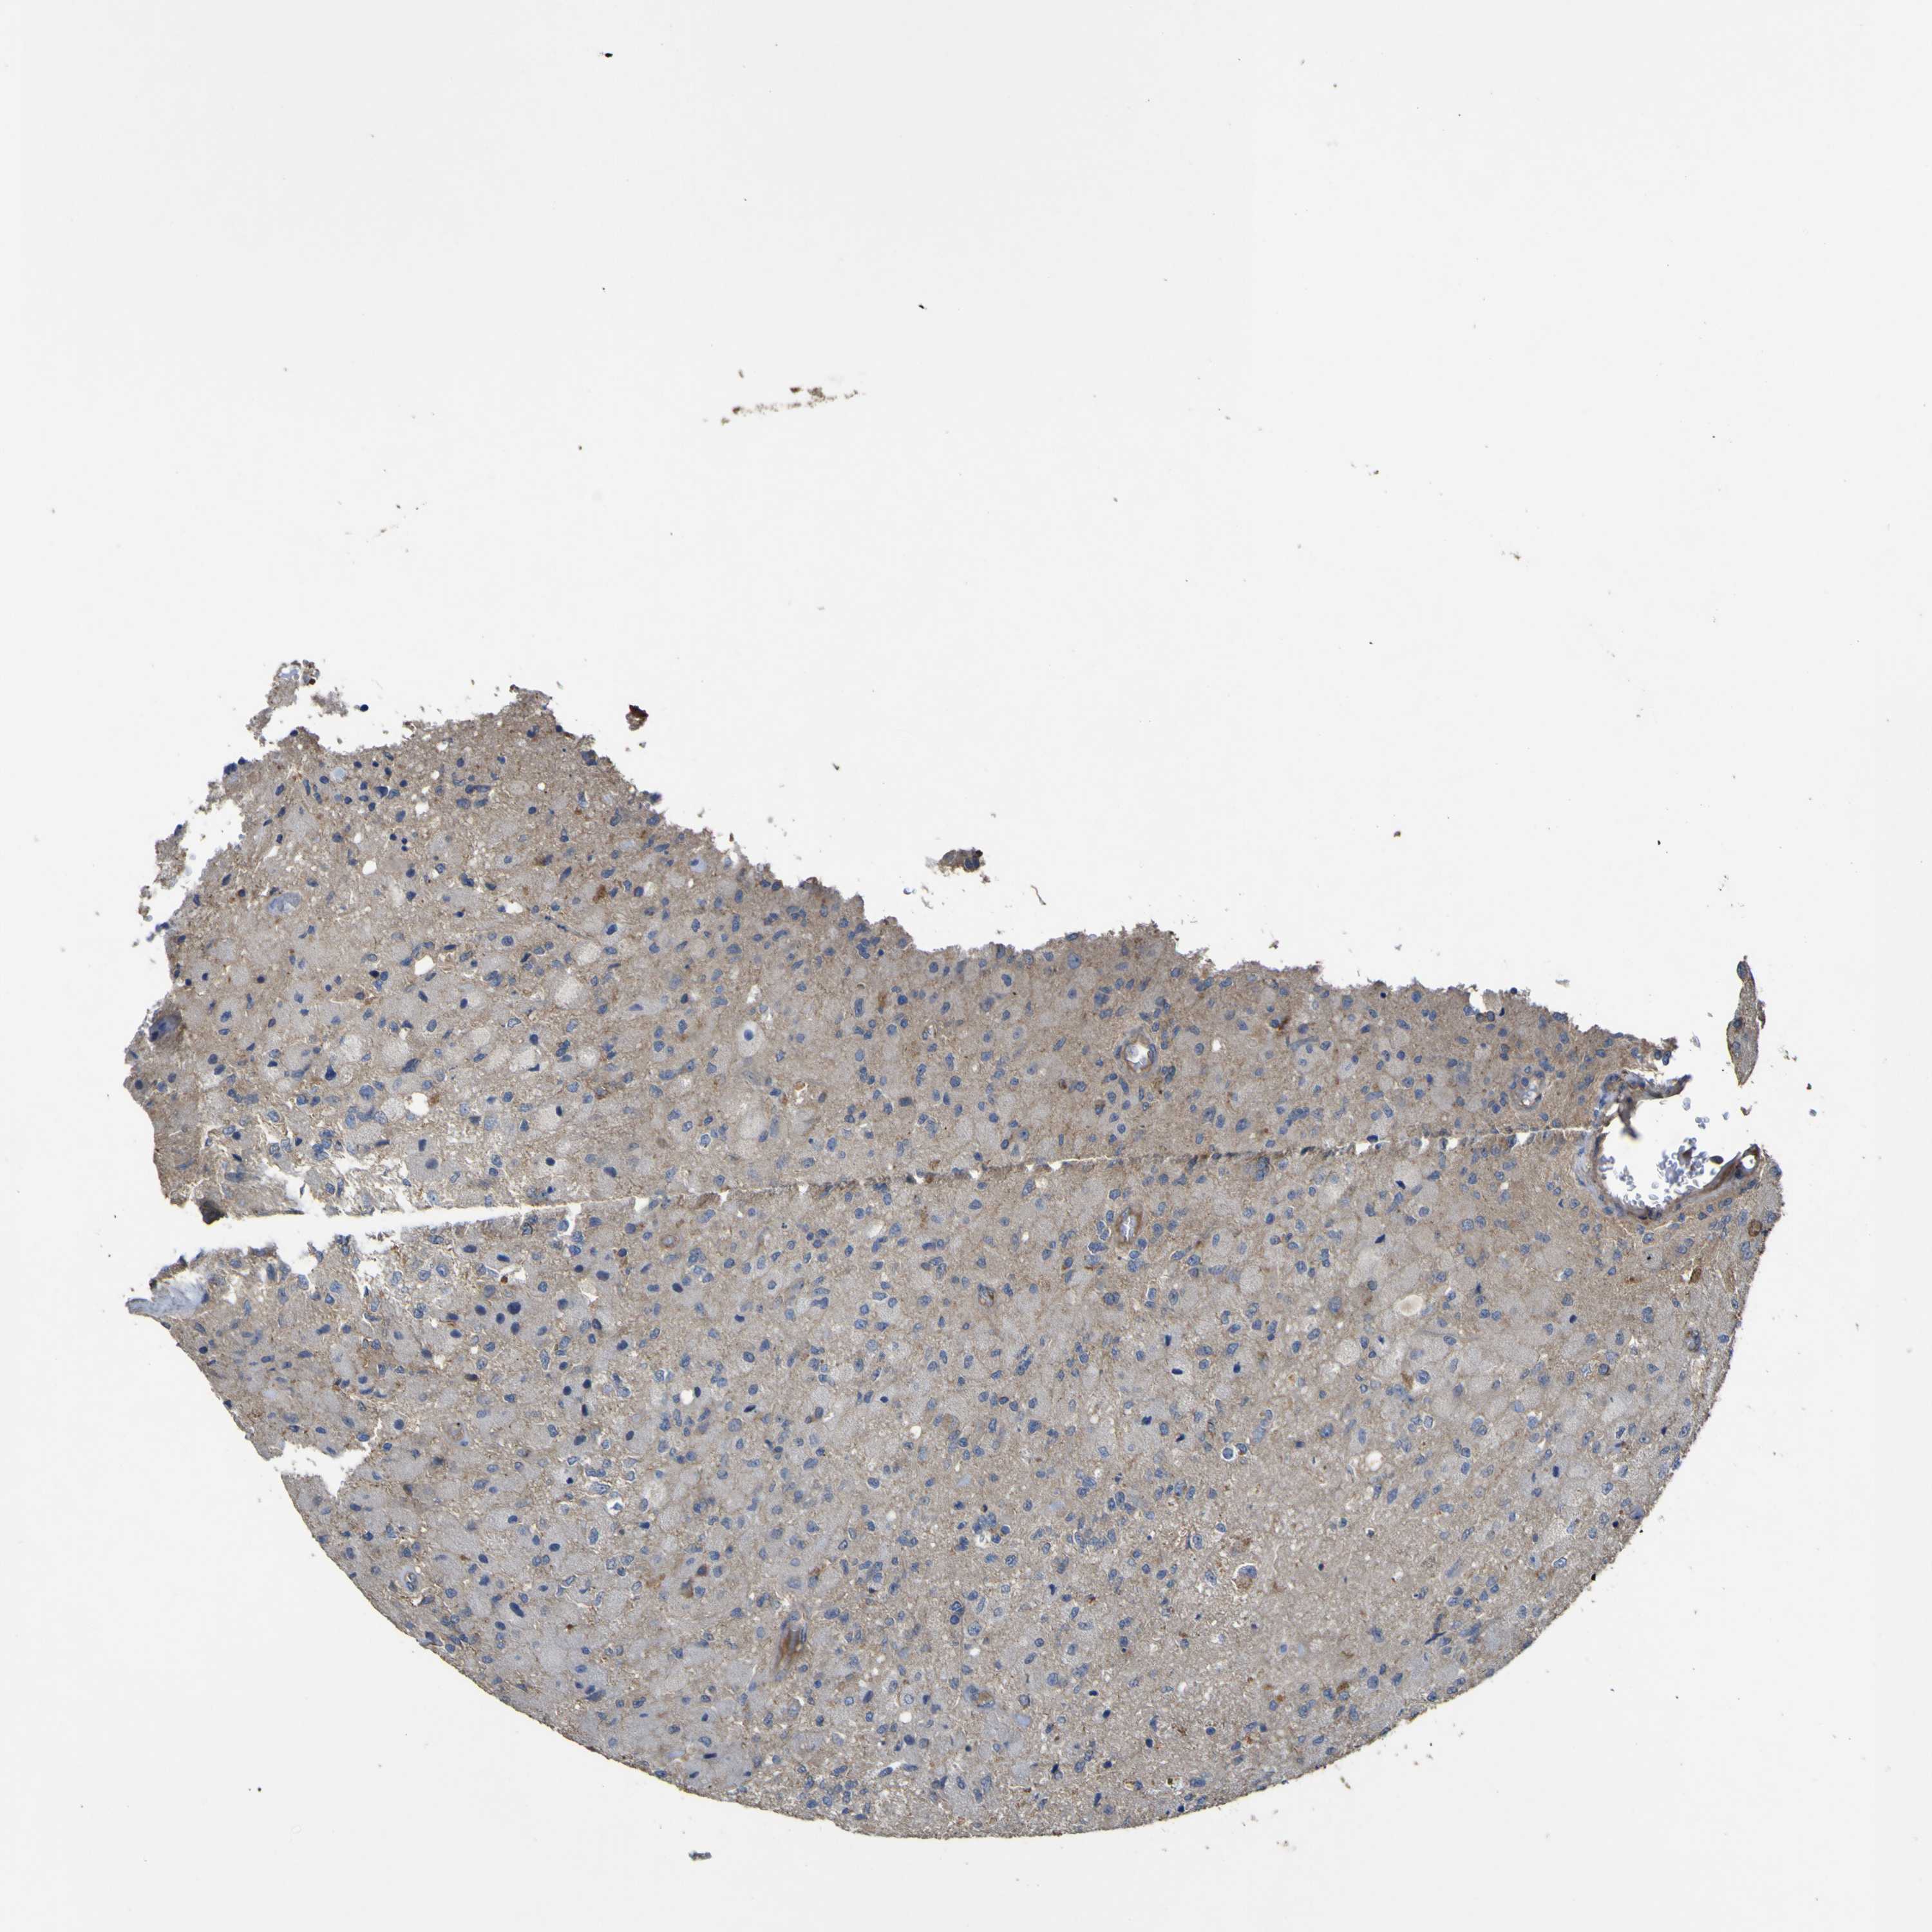

GLIOMA - Protein expressioni

A mouse-over function shows sample information and annotation data. Click on an image to view it in a full screen mode. Samples can be filtered based on level of antibody staining by selecting one or several of the following categories: high, medium, low and not detected. The assay and annotation is described here.

Note that samples used for immunohistochemistry by the Human Protein Atlas do not correspond to samples in the TCGA dataset.

Antibody stainingi

Antibody staining in the annotated cell types in the current human tissue is reported as not detected, low, medium, or high, based on conventional immunohistochemistry profiling in selected tissues. This score is based on the combination of the staining intensity and fraction of stained cells.

Each image is clickable and will lead to virtual microscopy that enables deeper exploration of all samples and also displays staining intensity scores, fraction scores and subcellular localization as well as patient and tissue information for each sample.

Antibody HPA012948

Staining

High

Medium

Low

Not detected

Intensity

Strong

Moderate

Weak

Negative

Quantity

>75%

75%-25%

<25%

None

Location

Nuclear

Cytoplasmic/membranous

Cytoplasmic/membranous,nuclear

Glioma, malignant, High grade

Glioma, malignant, Low grade